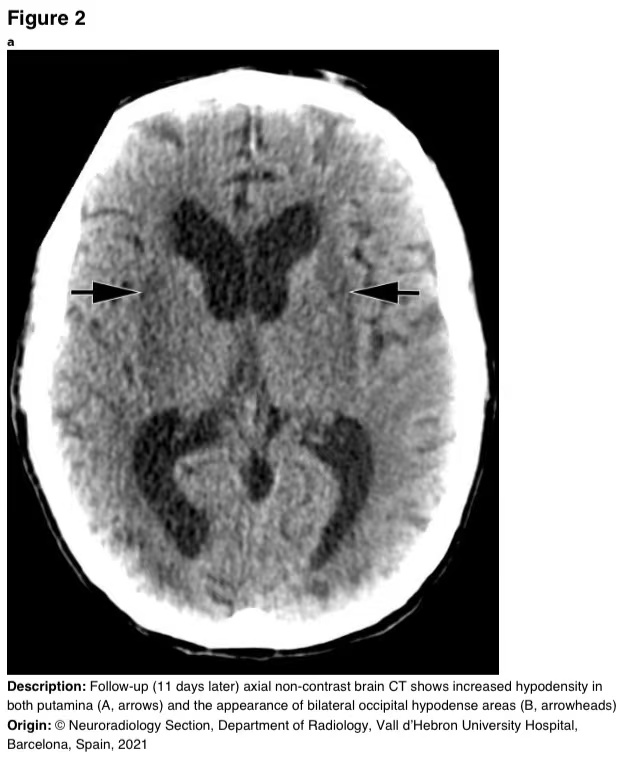

11天后随访获得的脑CT显示,双侧枕下皮质下白质的壳核低密度以及低密度区域增加(图2)。

图2 a-b 随访(11天后)脑CT平扫显示壳核低密度增加(A,箭头)和双侧枕下低密度区(B,箭头)。